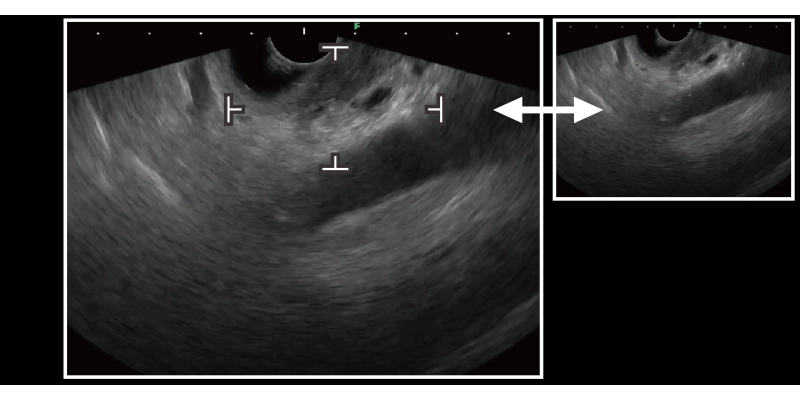

膵臓認識支援機能 メイン画面 ON

膵臓認識支援機能 サブ画面 ON